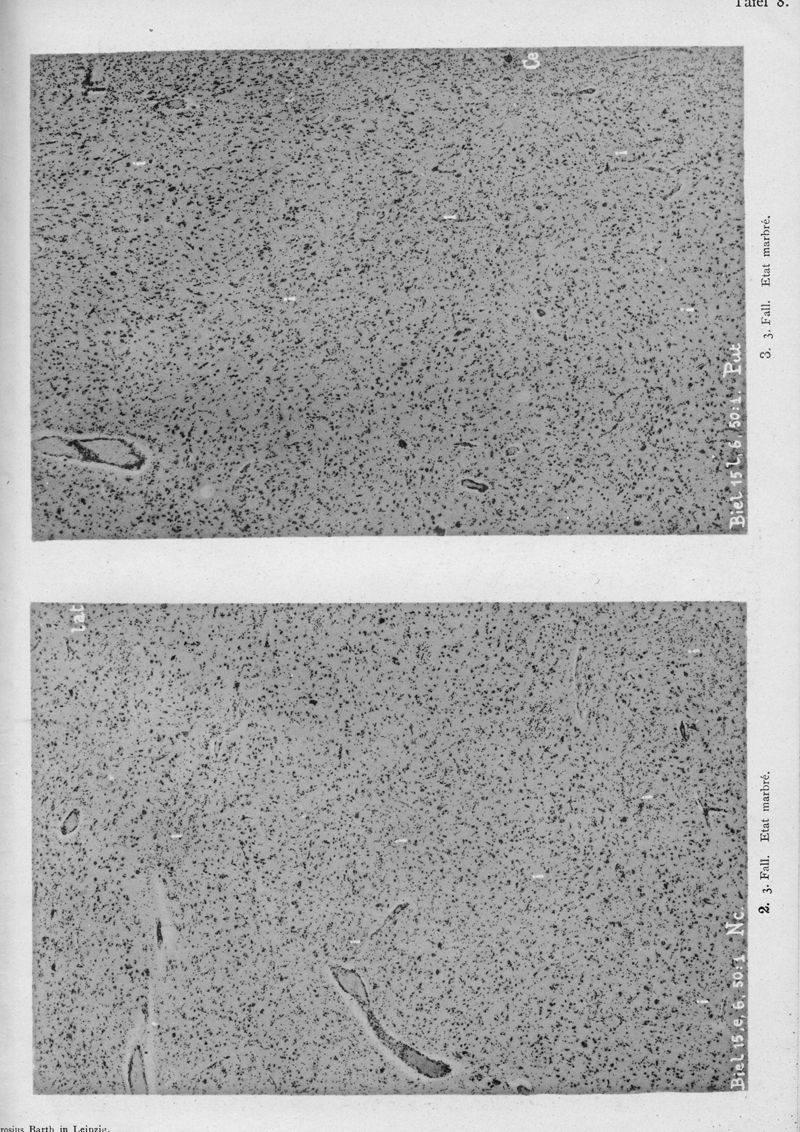

VOGT, Cécile / VOGT, O.

In : Journal für Psychologie und Neurologie,

1920, Vol. 25, pp. 627-846